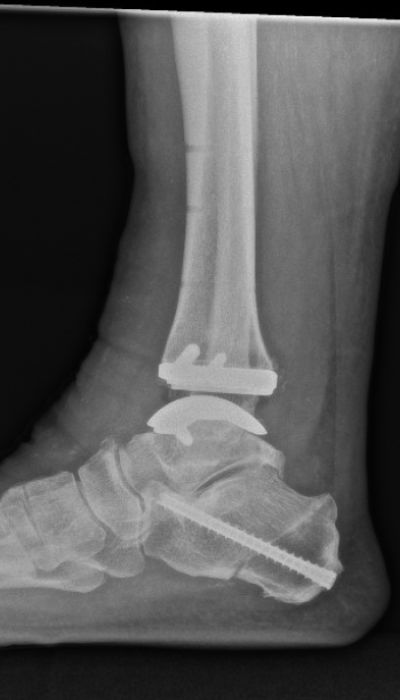

Röntgenaufnahme des rechten Sprunggelenks mit eingesetzter Prothese im Stand zur postoperativen Kontrolle.

Abbildung a-d: 78-jähriger Patient mit viertgradiger OSG-Arthrose bei varischer Verkippung des Talus. Verlaufskontrolle 6 Wochen nach Implantation der OSG-TEP. Noch erkennbare Bohrlöcher in der Tibia von der Ausrichtungslehre der OSG-TEP.

Seitdem ist eine umfangreiche technische Entwicklung des Designs, der Implantatbeschichtung und der Implantationstechnik vollzogen worden (17-19). Lange hatte die Endoprothetik des OSG mit kurzen Standzeiten und Komplikationen zu kämpfen. Die heute zur Verfügung stehenden Konzepte kommen den Standzeiten der Hüft- und Knieendoprothesen immer näher (20). Während früher Fehlstellungen im OSG als Ausschlusskriterium betrachtet wurden, erfolgt heute die Achskorrektur durch Osteotomie ein- oder zweizeitig im Rahmen der Implantation der Endoprothese (Abbildung c,d). Wichtig ist die sorgfältige Behandlung von Inkongruenzen im Sprunggelenk mit Wiederherstellung des korrekten Alignments. Wird die Fehlstellung regelrecht behoben, sind die biomechanischen Resultate vergleichbar mit denen ohne vorbestehende Inkongruenz (21). Studien konnten zeigen, dass bei Varus-Fehlstellung bis zu 30° präoperativ nach Prothesen-Implantation mit erfolgtem Re-Alignment kein relevanter Unterschied im funktionellen Outcome zu betrachten ist (22).

Der Patient, 78 J., männlich, stellte sich mit seit Jahren bestehenden, progredienten Schmerzen im rechten OSG in der Sprechstunde vor. Klinisch zeigte sich eine plantigrade Fußstellung bei varischer Rückfußachse. Die Beweglichkeit war eingeschränkt, Dorsal-/Plantarflexion OSG rechts 0/0/35°. Motorik, Durchblutung und Sensibilität waren intakt. Im Röntgen wurde eine viertgradige OSG-Arthrose bei ausgeprägter varischer Verkippung des Talus und Synostose des distalen Tibiofibulargelenkes deutlich. Nach Ausschöpfung der konservativen Therapiemaßnahmen stellten wir die Indikation zur Implantation einer OSG-TEP mit ergänzender minimalinvasiver Umstellungs­osteotomie des Calcaneus. Postoperativ erfolgte die Mobilisation im langen Walker mit Bodenkontaktlauf. 6 Wochen postoperativ lagen reizlose Narbenverhältnisse vor. Das Bewegungsausmaß stellte sich mit Dorsal-/Plantarflexion 10°/0°/40° verbessert dar. Es bestand noch eine moderate Schwellneigung. Im Röntgen zeigte sich eine gut integrierte OSG-Endoprothese bei unveränderter Implantatlage und knöchern fusionierter Calcaneus-Osteotomie. Von Seiten des Patienten bestand eine deutliche Reduktion der Schmerzen und subjektive Zufriedenheit. Anschließend erfolgte eine rasche Steigerung der Belastung bis zur Vollbelastung ohne Walker und Gehstützen.